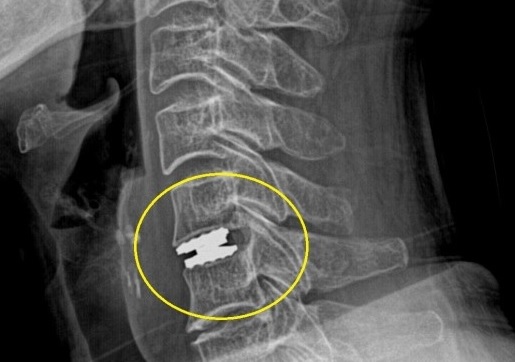

인공디스크 치환술

목 인공디스크 치환술 ADR(Artificial Disc Replacement) 은 손상된 디스크를 정상적인 디스크와 동일한 기능을 하게 합니다.

신경을 압박하고 있는 수핵 (디스크)를 제거하여 신경감압, 증상호전 도모 제거한 디스크 대신 인공디스크 삽입하여 탄력성 및 안정성 유지를 목적으로 합니다. 고정하는 수술이 아니므로 수술 후 관절의 기동성이 그대로 유지되어 움직임이 자유롭습니다. 목디스크 통증으로는 극심하게 아프며. 밤에 잠을 못 잘 정도로 힘듭니다. 우측 팔이 떨어져 나갈 듯한 통증, 후경부 통증. 우측 팔 통증이 심하게 나타납니다.

전신마취하에 이뤄지며 ,전방으로 접근하고 현미경하 디스크 및 신경압박 구조물 제거한 뒤 인공디스크 삽입/고정합니다. 고정하는 수술이 아니므로 수술 후 관절의 기동성이 그대로 유지되어 움직임이 자유롭습니다.